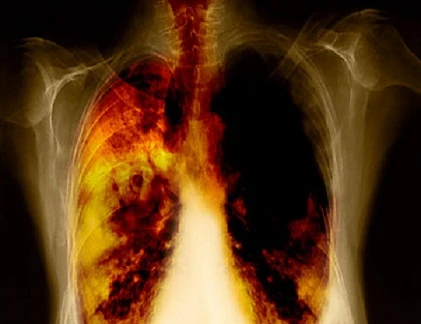

Các triệu chứng của ung thư phổi lúc đầu thường giống với bệnh viêm họng thông thường. Chúng ta cần phân biệt chúng để có những cách chữa trị đúng nhất.

Ung thư phổi là căn bệnh nguy hiểm. Vì vậy bạn cần phát hiện sớm bệnh để chữa trị kịp thời.